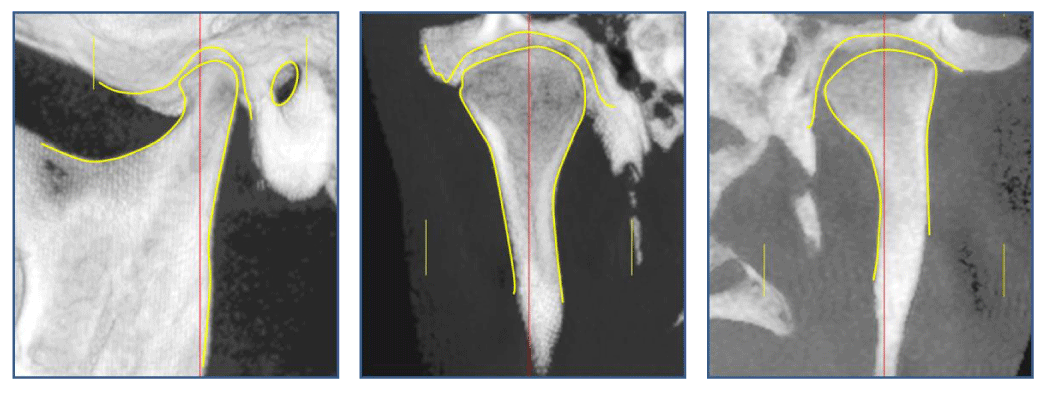

TMJ pre-orthodontic, cephalometric and routine tests were indicated. Patients were informed about procedures and consented to the present study. In the differential diagnosis of temporomandibular joint pathology, age and sex were not significant for this investigation. A total of 38 joints were evaluated as independent units [Figure 3a,b,c].

Figure 3a-c: CBCT images analyzed with Dolphin Imaging 11.7 Software. Sagittal cut 1 - a, coronal cuts1 - b and 1 - c

Figure 4a-c: Hard structures. Sagittal view a. Coronal views b - c

Taking as a reference the major condylar axis in a horizontal plane, a sagittal cut was reconstructed, which indicates the following sections: external auditory meatus, articular eminence, mandibular condyle, fossa and 2/3 of the mandibular ramus (Figure 4a). Acoronal cut shows the mandibular condyle, neck, fossa, and 2/3 of the mandibular ramus (Figure 4 b-c).